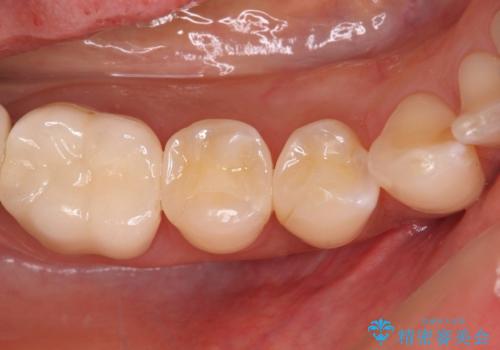

歯肉が少し退縮していたため、補綴治療のやり直しにより歯が少し長く見えるようになりましたが、自然な口元に仕上がり、患者様には大変満足していただきました。

定期的にラグビーをされるとのことなので、マウスピースの装着をかかさないようにお伝えしました。